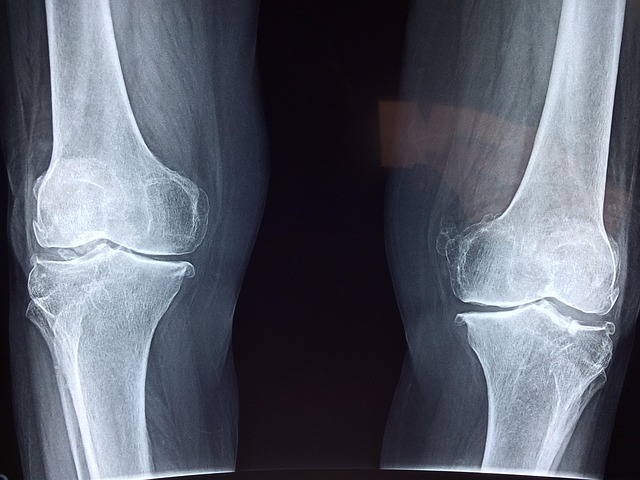

Albers-Schönberg disease, also known as adult autosomal dominant osteopetrosis or marble bone disease, is a hereditary disorder characterised by increased bone density throughout the skeleton. Although the bones appear markedly dense on imaging, their structure is abnormal, and they may be brittle, leading to fractures, bone pain, and complications related to the excessive bone mass. Early recognition and management of complications are important to preserve … Continue reading Albers-Schönberg disease